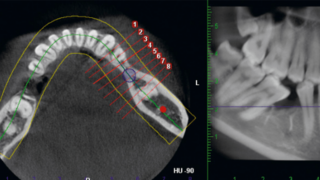

3次元CT検査とは?見えない部分まで把握する歯科の精密検査

きずな歯科では、3次元CT検査によって口腔内を立体的に撮影。顎の骨や歯の状態を正確に把握し、見えない病巣も早期発見。短時間で負担も少なく、安心の検査です。